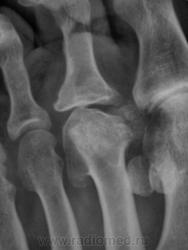

Похоже на болезнь Келлера -2 .

А почему похоже? "Композиторов" иногда не помню, но если асептический некроз головок 2-4 плюсневых костей это Келлер-2, то так и есть.

+ поперечное плоскостопие.

Очень похоже, хотя болеет чаще женский пол!

Только очень старый, сейчас уже просто выраженный артроз.